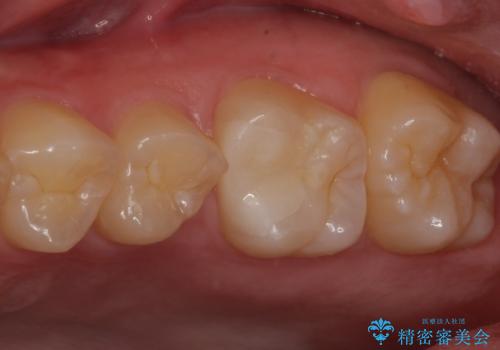

見た目、噛み合わせともに満足していただけました。

ラバーダム防湿を行い、セラミックの接着をすることで、唾液や血液などの接着阻害因子を排除することができます。